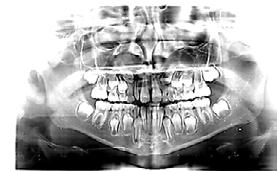

b) Análisis radiográficos, periapicales, ortopantomográficos, oclusales, lateral de cráneo, anteroposterior de cráneo.

c) Estudio y análisis tomográfico en tercera dimensión del cráneo a nivel maxilar y mandibular (Figura 24).

24.

Figura

1. La existencia y presencia de todos los elementos anatómicos craneodentofaciales (Figura 26).

Al estar ausente algún germen dental (como los laterales superiores permanentes y/o premolares de ambas arcadas, “los de mayor incidencia”),10 se inhibe la estimulación adecuada en el desarrollo óseo de esa zona específica, ya que al no existir el germen dental, la matriz ósea inhibe su crecimiento en esas zonas en específico11 (Figura 29).

Diagnóstico y tratamiento ortodóntico interceptivo como prevención en la inclusión del canino

maxilomandibulares, 17 las cuales propician alteraciones en el proceso del intercambio dentario; en la que una reducción de los espacios necesarios para el acomodo de los caninos y de otros órganos dentales en las arcadas, retrasa e impide que el impulso natural propio de la formación radicular como empuje fisiológico, impidiendo el desplazamiento y la erupción del canino en tiempo y una posición ideal dentro del arco dental (Figura 30).

Sumado a lo anterior, la retención generada dentro del macizo óseo basal altera su posición en angulación y dirección correcta de erupción. Situación que en ocasiones daña las raíces de los dientes adyacentes al canino y que finalmente podrá quedar incluido, en el peor de los casos, cuando no encuentra una salida de emergencia hacia el paladar o el vestíbulo12 (Figura 31).

Figura 29.